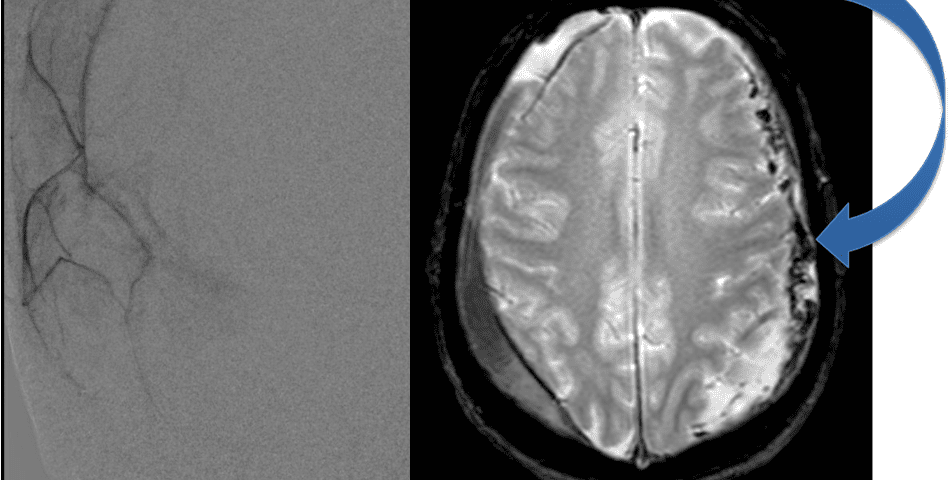

Care must be taken to place the microcatheter within a safe position for embolization, with special attention to potential collateral branches to the orbit/eye via sphenoid or meningo-lacrimal branches (which may cause vision loss) or petrosal branches supplying the geniculate ganglion, the tympanic portion of the facial nerve, and often the trigeminal nerve via a branch coursing along the greater petrosal nerve. Once a safe position in the main trunk of the MMA, or superselectively in each of its divisions is achieved, embolization is performed until stasis of contrast and dense contrast staining of the dura is observed within the embolized vascular beds.7

Figure 8. Dense contrast staining of vascular membranes during embolization.